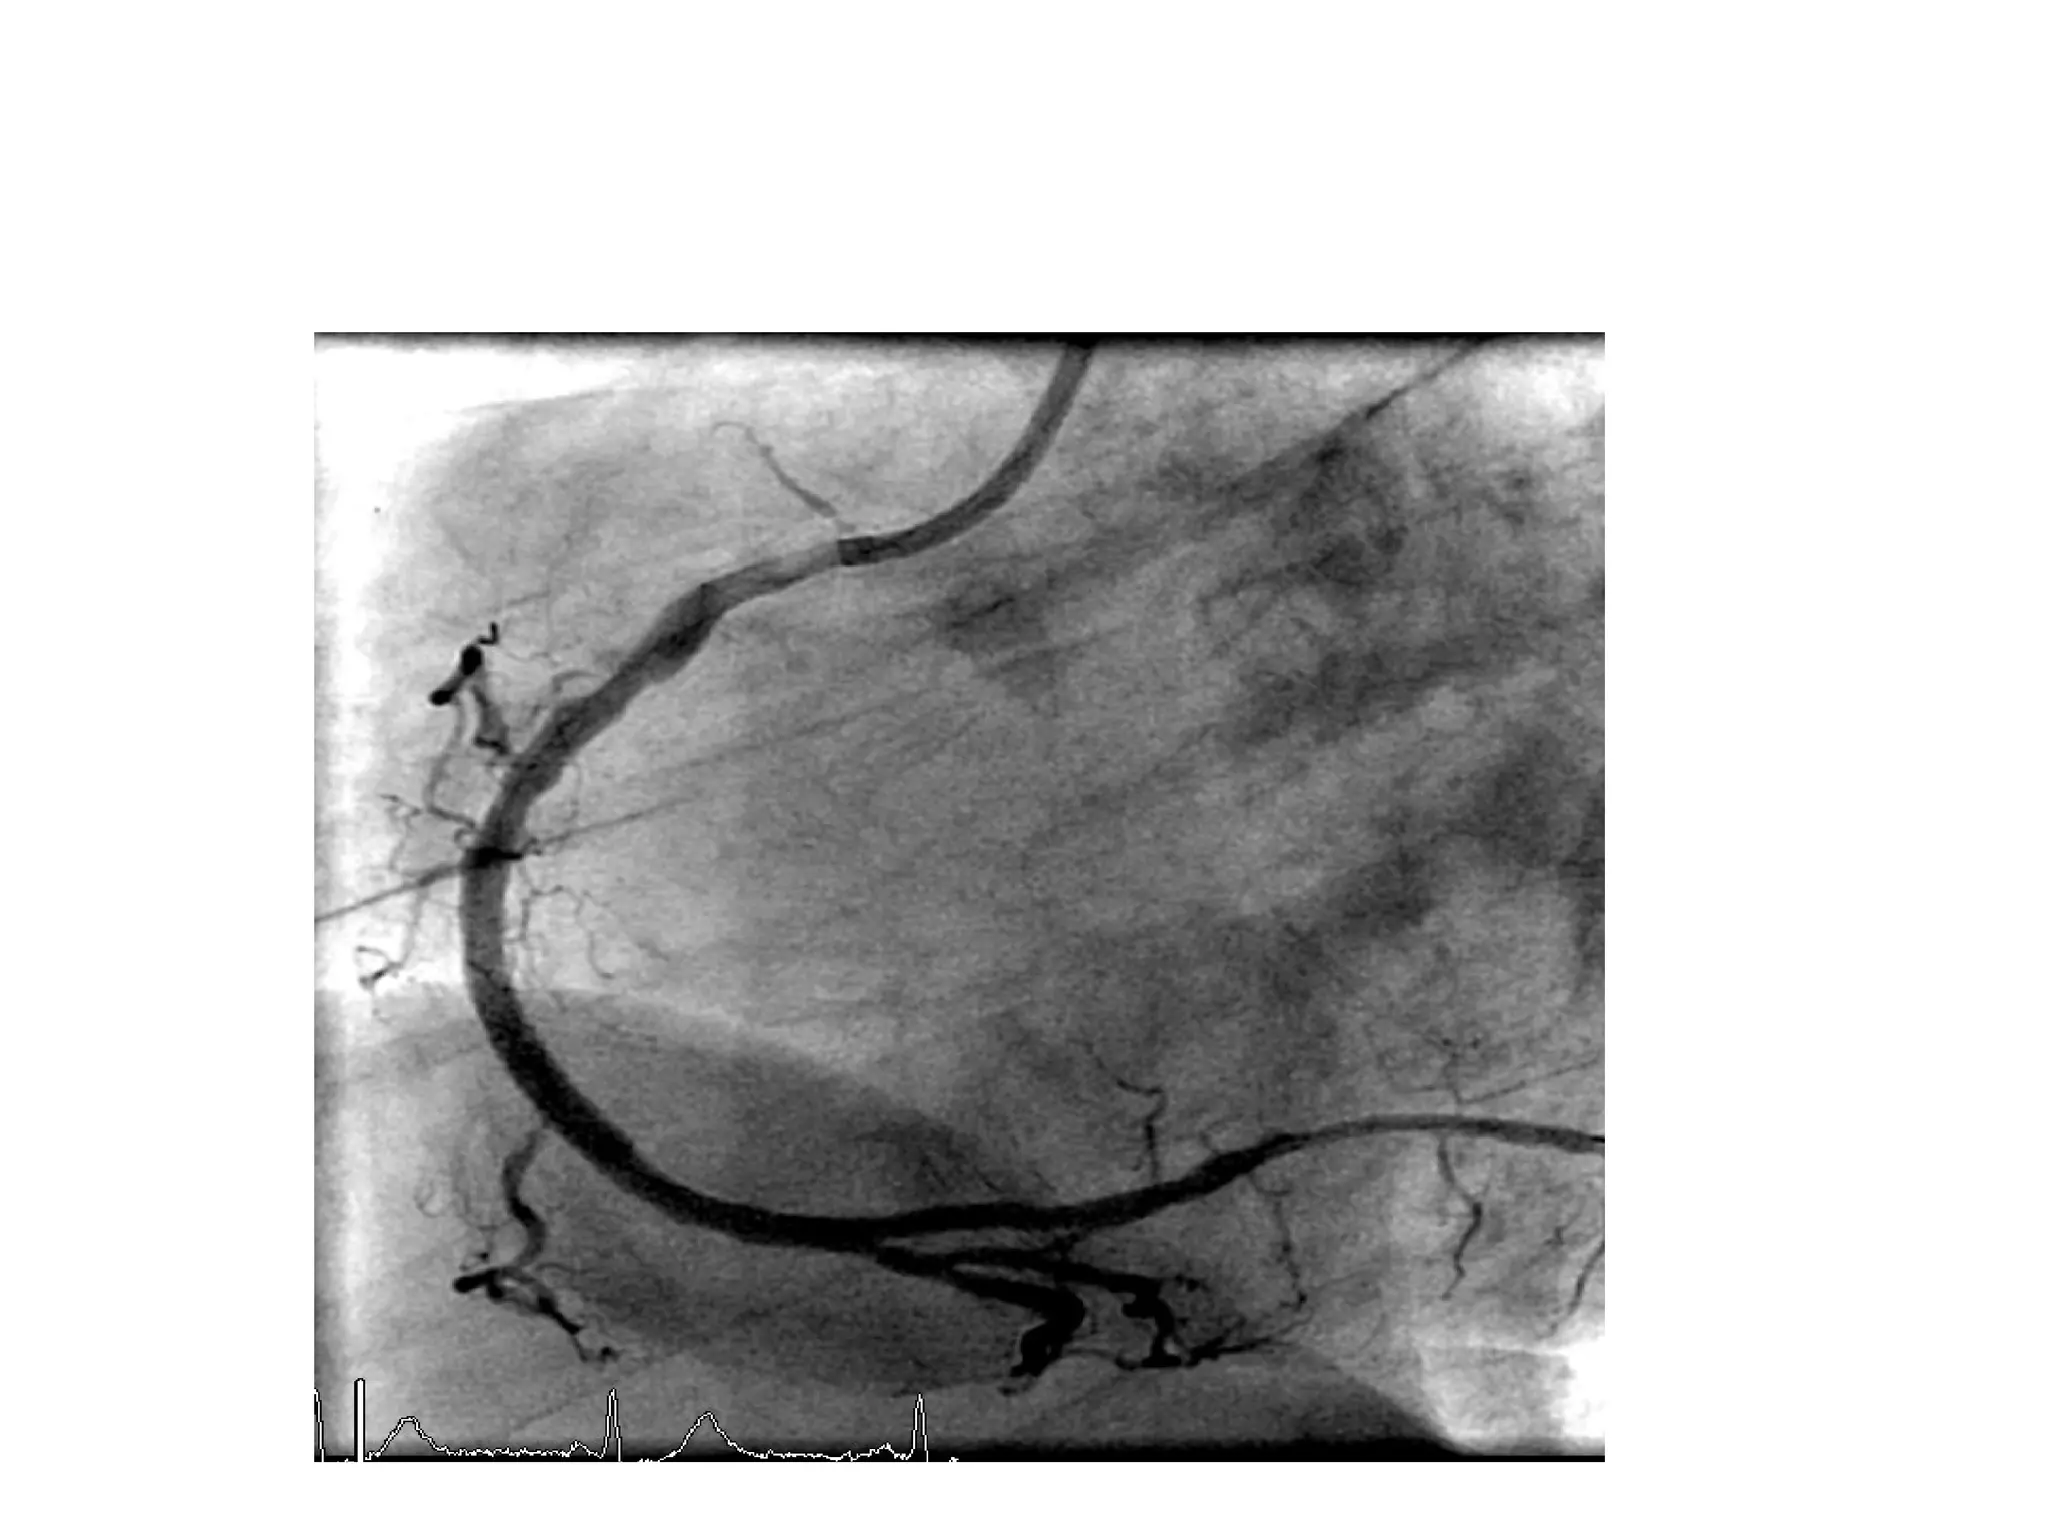

A 43-year-old man presented with chest pain and was diagnosed with an acute inferior ST elevation myocardial infarction with evidence of right coronary artery occlusion but no right ventricular involvement; he underwent primary percutaneous coronary intervention of the mid right coronary artery, which had a clot. The same patient had a complex lesion in the left anterior descending artery and its diagonals requiring staged percutaneous coronary intervention. A 55-year-old woman with diabetes and chest pain was found to have severe reversible ischemia in the territories of the left anterior descending artery and right coronary artery on nuclear stress testing, with normal circumflex artery area; coronary angiography revealed a critical proximal lesion in the left anterior descending artery.